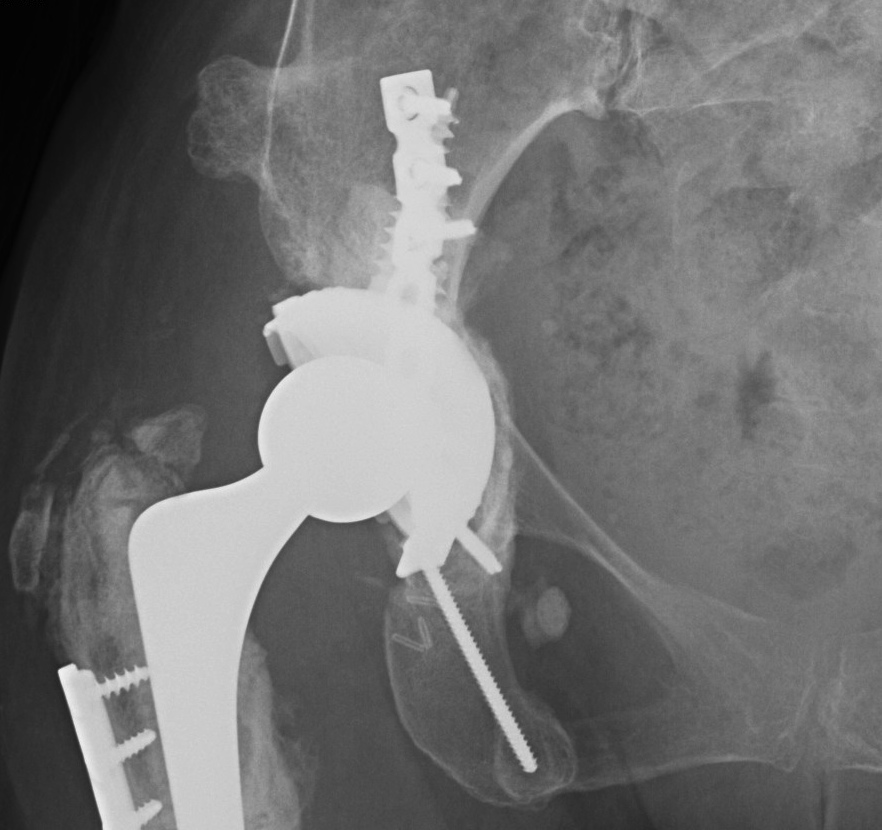

Pelvic discontinuity

1. Plate and bone graft posterior column

2. Plate + Cage reconstruction

3. Cup Cage Reconstruction

Technique

- large tantalam cup inserted for reconstitution of discontinuity

- bone graft inserted

- cage, cement in cup